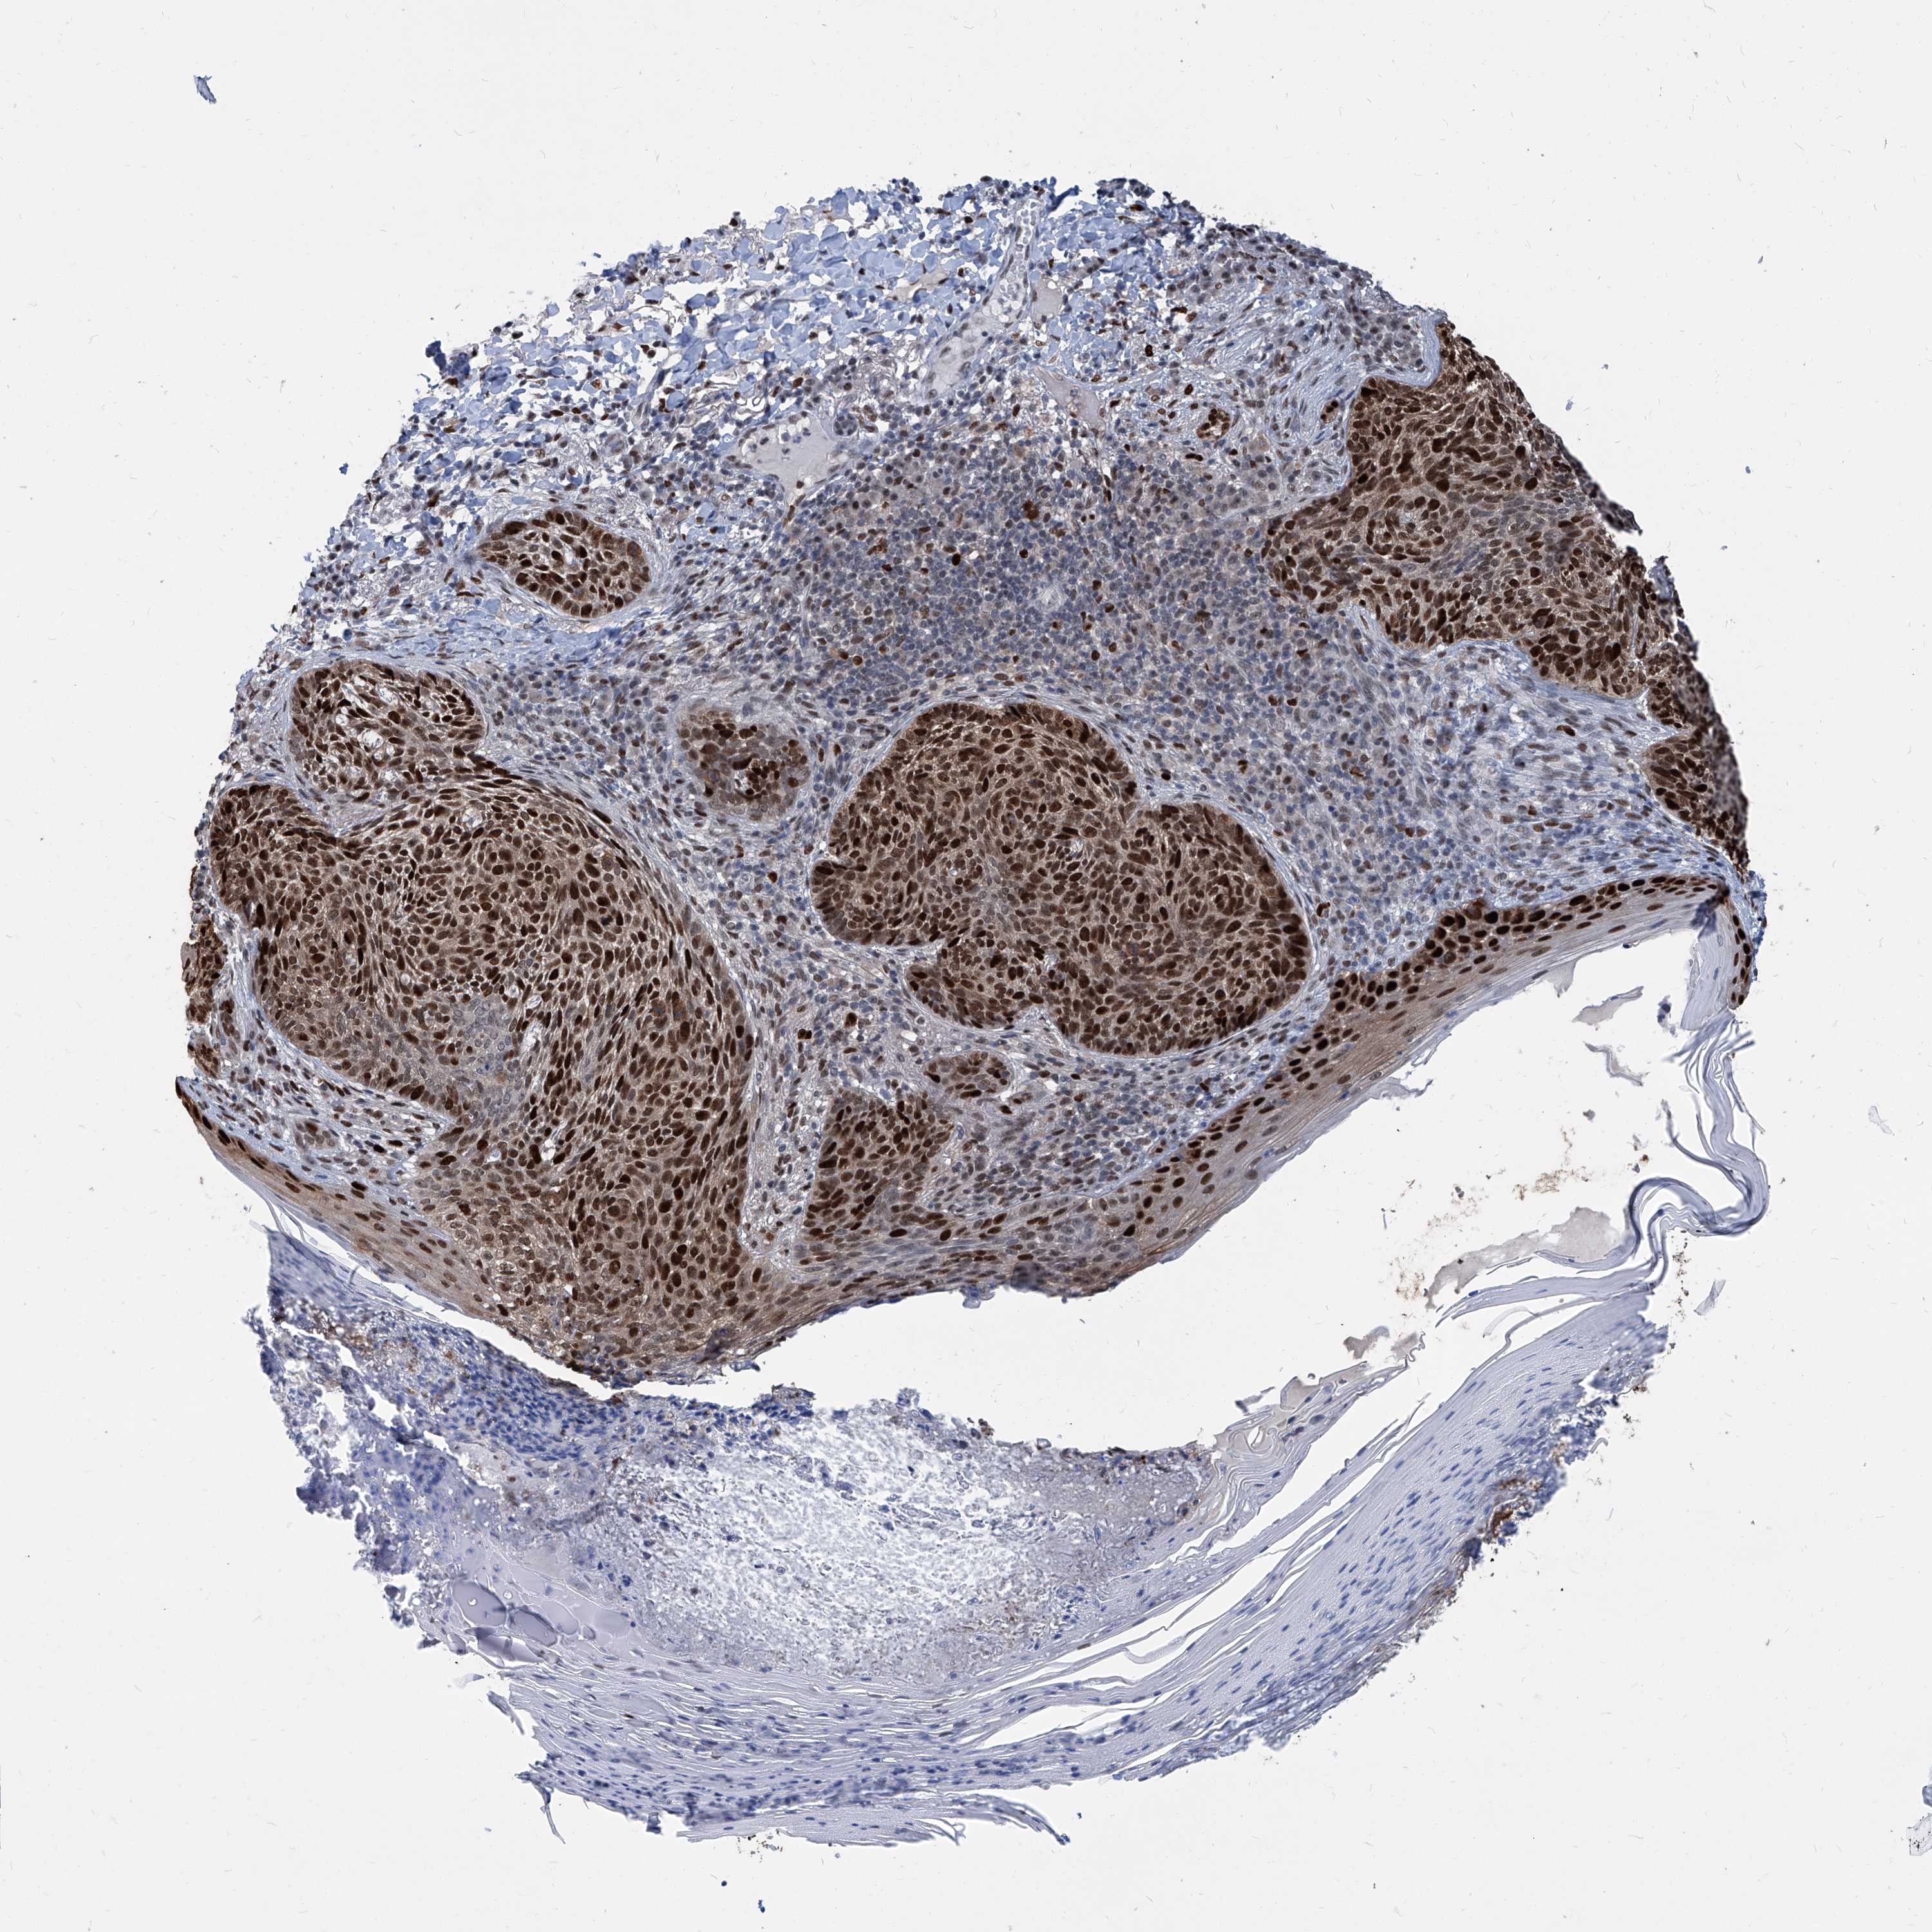

Basal cell and squamous cell cancer

SKIN CANCER - Protein expressioni

A mouse-over function shows sample information and annotation data. Click on an image to view it in a full screen mode. Samples can be filtered based on level of antibody staining by selecting one or several of the following categories: high, medium, low and not detected. The assay and annotation is described here.

Each image is clickable and will lead to virtual microscopy that enables deeper exploration of all samples and also displays staining intensity scores, fraction scores and subcellular localization as well as patient and tissue information for each sample.

Basal cell carcinoma

Squamous cell carcinoma, NOS

Squamous cell carcinoma, metastatic, NOS